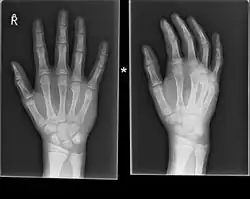

Boxer fracture -

Boxer fracture of the 4th and 5th knuckles